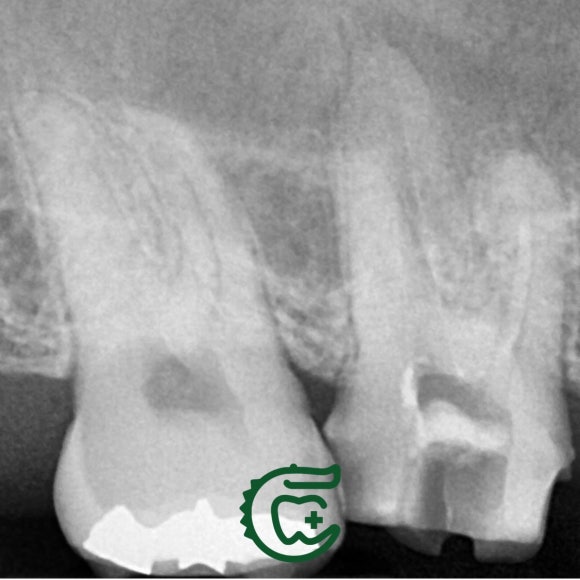

타치과에서 재신경치료를 받으시던 도중에

저희 치과로 오셨습니다.

이전 치과들에서 신경치료를 지속했음에도

뾰족하게 해결이 안되었던 이유는

바로 숨어있던 신경관에 있었습니다.

미세 현미경 하에서 이전 치료들에서 놓친

신경관을 찾아 청소해주니,

그 즉시 증상도 사라지고

상악동 내의 염증 소견도 사라졌네요.